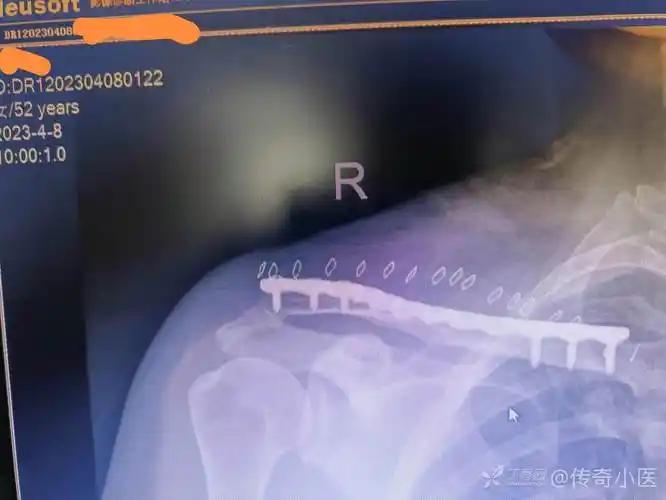

锁骨锁定钢板nice结复位固定锁骨中段粉碎性骨折